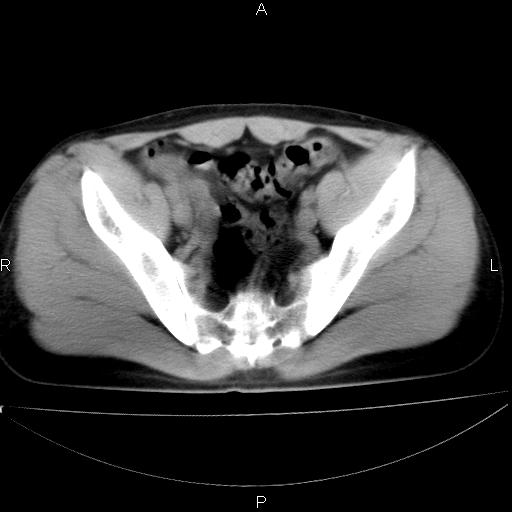

男 25岁 自述 尿频尿急,排尿困难20多天.无腰痛, b超说左肾盂轻度积水,左输尿管上端扩张.未见结石影. ct我看双侧肾盂轻度积水,双输尿管上端都扩张,大家看看能看见结石吗?

考虑肾外肾盂 前列腺轻度肿大 密度欠均 考虑炎性改变

箭头所指不是输尿管,壶腹型肾盂。

肾外肾盂,必要时+c